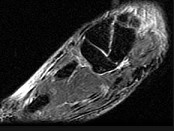

- 单项选择题女,25岁, 扭伤后足中部痛,结合图像, 最可能的诊断是 ( )

A、內侧楔状骨骨折

B、外侧楔状骨骨折

C、足舟骨骨折

D、中间楔状骨骨折

E、未见异常